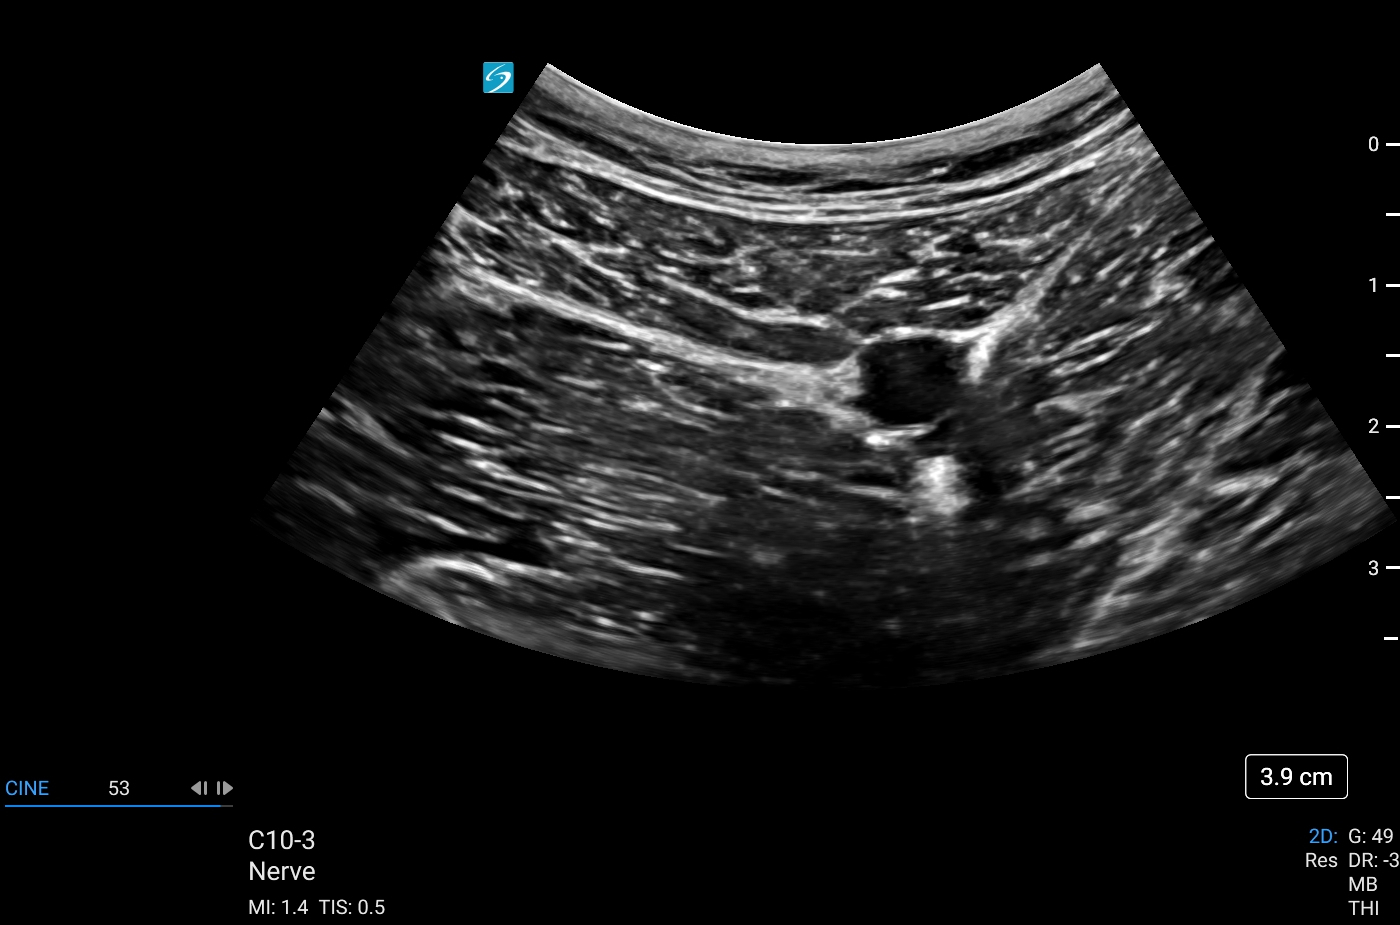

Sonosite LX, bakım noktası ultrasonunu çeşitli ortamlarda daha kapsayıcı ve erişilebilir hale getirerek klinisyenlerin deneyimini yükseltiyor. Sonosite LX, optimum hasta bakımı için en gelişmiş görüntü netliğimizi ve ses kontrolümüzü bünyesinde barındırıyor. Eğitim potansiyeliyle dolu olan bu ürün, her seviyedeki kullanıcıya her zamankinden daha fazlasını keşfetme gücü veriyor.

- Klinik ekip üyeleriyle kolay görüntüleme ve hastalarla konsültasyon için büyük, uyarlanabilir klinik ekranda gelişmiş görüntü netliği